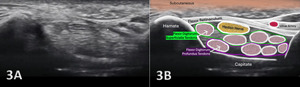

The median nerve is clearly identifiable in SAX by a well circumscribed ovoid structure with hypoechoic fascicles in a honeycomb-like pattern deep to the roof of the carpal tunnel, the flexor retinaculum, and more superficial to the flexor digitorum superficialis and flexor digitorum profundus tendons. The median nerve is also very compressible and will alter its shape depending on the volume of the anatomical spaces with which it courses. The median nerve cross-sectional area (CSA) can be measured in four sites: 1) the proximal border of the pronator quadratus muscle, 2) proximal to the carpal tunnel inlet, 3) at the tunnel inlet, and 4) at the tunnel outlet.9

The median nerve begins as the extension of the medial and lateral cords of the brachial plexus in the axillary region. It descends in the arm lateral to the brachial artery until the insertion of the coracobrachialis, where it crosses in front, and in rare cases, behind the artery to move to the medial side of the arm near the anterior cubital fossa. At that location, it runs behind the lacertus fibrosus and is separated from the joint by the brachialis muscle. The median nerve received its name from the middle position at the end of the brachial plexus and the forearm.5 As it descends further in the forearm, it runs between the two heads of the pronator teres. From that point it runs beneath the flexor digitorum, laying on the flexor digitorum profundus more superficially as it passes underneath the transverse carpal ligament (flexor retinaculum) into the palm. At the hand, the median nerve gives motor branches to the thenar eminence, and second lumbrical muscles, as well as sensory branches to the radial half of the palm and the radial three and half digits.6 Its motor function is to the flexor aspect of the forearm, hand, and thumb to innervate the pronator teres, palmaris longus, flexor digitorum superficialis, flexor carpi radialis, and via the anterior interosseus nerve (AIN), the flexor pollicis longus, the flexor digitorum profundus, and the pronator quadratus.